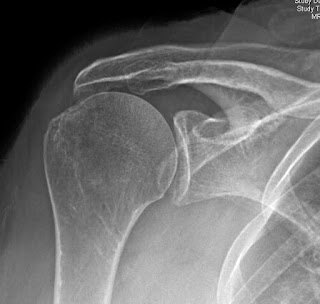

Comment: Our practice is to obtain a preoperative true anteroposterior radiograph in the plane of the scapula and then use that image to envision a line perpendicular to the glenoid center. At surgery, the drill for the central screw of the baseplate is oriented by eye with a slight inferior tilt in reference to this perpendicular to the glenoid center. No guides or special instrumentation is used. In cases where the preoperative true anteroposterior radiograph in the plane of the scapula indicates a superior inclination of the perpendicular to the glenoid center, the angle of the drill is adjusted accordingly.

This approach is shown for the left and right shoulders of a patient having had a failed hemiarthroplasty on one side and pseudo paralysis on the other.